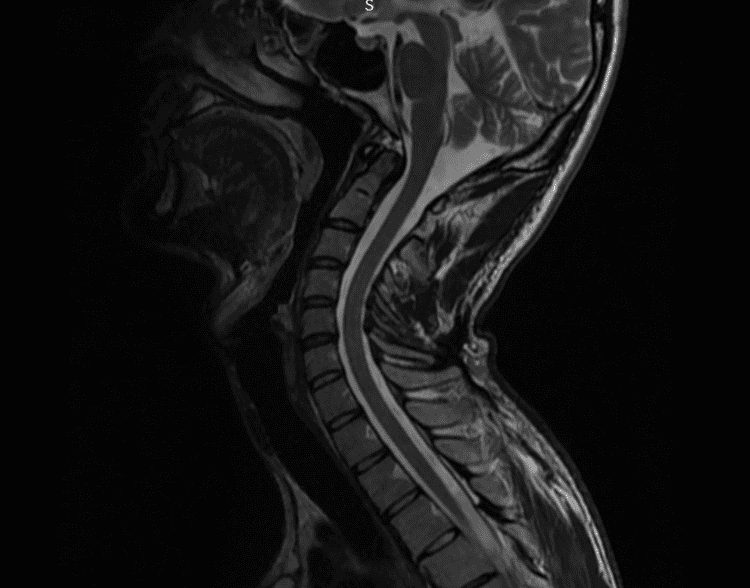

Resonancia Magnética Nuclear (RMN)

La RMN es una herramienta avanzada que permite obtener imágenes muy precisas de los tejidos blandos, incluidos músculos, ligamentos, discos intervertebrales y nervios. Esta prueba es fundamental para diagnosticar problemas cervicales complejos que pueden no ser evidentes en las radiografías o en la TAC. También es útil para evaluar el estado de la médula espinal y posibles compresiones nerviosas.